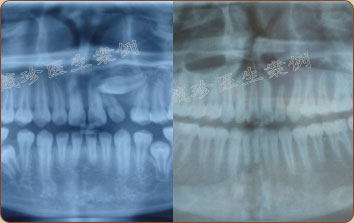

三颗埋伏牙无法正常萌出

症状:牙齿稀疏,三颗埋伏牙

难点:左侧2号牙和3号牙之前的

横向埋伏牙无法正常萌出

在小王的案例上,李藏珍医生制定了不拔牙,牵引埋伏牙入牙列,关闭间隙的矫治方案。一次性解决了小王牙列稀疏,牙齿无法正常萌出的难题。